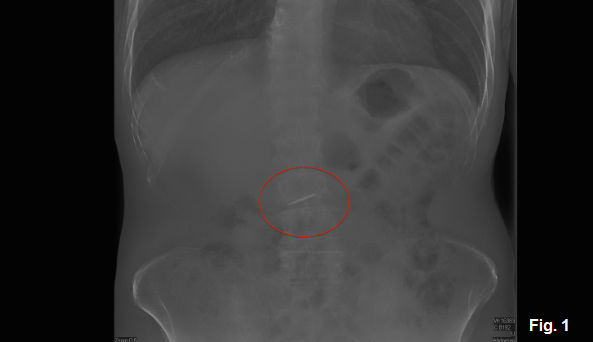

If the patient is asymptomatic, it’s important to remain calm, reassure them and inform them about the complication and the need for immediate medical examination. Generally, frontal and lateral chest and/or abdominal radiographs should be used to locate the object.

It’s important to be aware that conventional radiography may be insufficient to locate items that are not sufficiently radiopaque. Radiolucent components or prostheses, such as those made from acrylic or composite resin, may require alternative imaging modalities. It’s crucial that clinicians characterize the object in terms of shape, size, and material when an accident occurs and pass that information on to the treating physician.